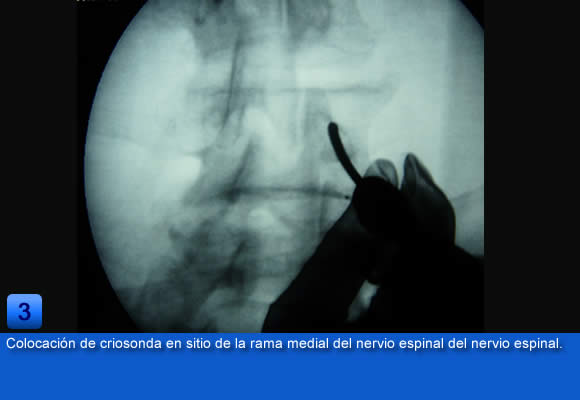

Estas medidas suponen un alivio satisfactorio para un gran número de pacientes, pero cuando no se obtiene un gran alivio del dolor a corto plazo, se puede optar por un tratamiento más selectivo como es la criodenervación percutánea facetaría lumbar, que permite un alivio mas duradero para que los pacientes puedan reanudar sus actividades cotidianas.

Como tratamiento sintomático es temporal y debe de ir acompañado de una reducación paralela de la espada. Pero una buena selección de los pacientes y una correcta indicación, considerando que la mayoría de las veces se aplica a pacientes con dolor lumbar crónico en el que suelen existir diversas implicaciones, obtienen resultados duraderos en el tiempo ayudando a disminuir el impactó sobre la actividad cotidiana de los pacientes con dolor lumbar crónico y el numero de pacientes que se han de someter a cirugía abierta espinal.